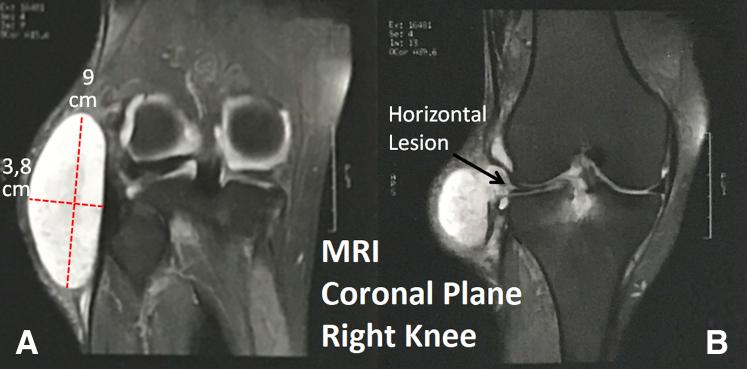

Parameniscal cysts are usually small cystic lesions, less than 2 cm in size, found along the meniscal periphery. They are rarely associated with extra-articular palpable mass. Magnetic resonance imaging is the diagnostic method of choice; giant meniscal cysts (>5 cm at its greatest diameter) are very rare, with few cases described in the literature. We describe a step-by-step open exeresis and arthroscopic meniscal suture technique for the treatment of a 9-cm giant parameniscal cyst located on the lateral side of the knee. Treatment of giant meniscal lesions requires caution during dissection and exeresis. Because acute meniscal lesions benefit from meniscal suture rather than meniscectomy, horizontal degenerative lesions may also present excellent results with repair techniques. We conclude that the combination of the open excision of the giant cyst with careful dissection and protection of neurovascular structures, combined with the arthroscopic meniscal suture, is a good strategy to approach such lesions.

半月板旁囊肿通常是小的囊性病变,大小小于2厘米,位于半月板周边。它们很少与关节外可触及的肿块相关。磁共振成像(MRI)是首选的诊断方法;巨大半月板囊肿(最大直径>5厘米)非常罕见,文献中仅有少数病例报道。我们描述了一种用于治疗位于膝关节外侧的9厘米巨大半月板旁囊肿的逐步开放性切除术和关节镜下半月板缝合技术。治疗巨大半月板病变在解剖和切除过程中需要谨慎。由于急性半月板损伤采用半月板缝合而非半月板切除术效果更佳,水平退行性病变采用修复技术也可能取得优异结果。我们得出结论,将巨大囊肿的开放性切除与仔细解剖和保护神经血管结构相结合,再加上关节镜下半月板缝合,是处理此类病变的良好策略。